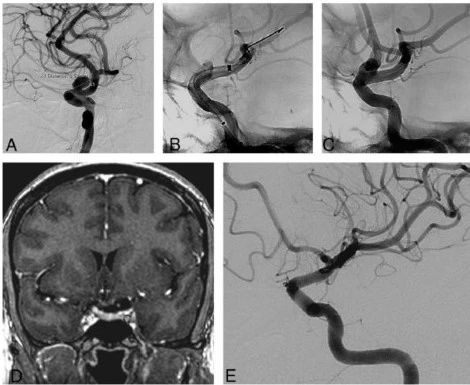

图1. A 左侧颈内动脉床突上动脉瘤;B 血流导向装置后造影显示装置远端贴壁不良(箭头);C 术后血管造影显示FD贴壁良好和FD内支架;D 术后3月冠状位增强MR显示瘤体未显影;E 6月造影随访显示动脉瘤完全闭塞。

总共68例患者76个动脉瘤,35个患者(41个动脉瘤)仅应用一枚surpass血流导向装置(非支架组),33个患者(35个动脉瘤)在surpass血流导向装置中植入一枚支架(支架组)。使用的支架类型包括:Atlas支架22例;冠脉支架8例;Neuroform、Enterprise和LEO 各1例。两组患者在年龄、性别、体重、血栓病史、吸烟、血小板抑制水平、高血压、高脂血症、糖尿病、恶性肿瘤、动脉瘤位置等方面没有显著差异,支架组的动脉瘤要比非支架组更大(14.8 :9.1 mm, P<.001=。在0-3月和3-6月时,两组病例动脉瘤闭塞率相似(73.3% :61.3%, P=.31, 以及 84.8% :70.2%, P=.14)。9-12个月的时候,支架组的动脉瘤闭塞率显著更高(93.9% :73.2%, P=.019),1年以上的末次随访中,两组病例动脉瘤完全闭塞率没有显著差异(93.9% :82.9%, P=.14)。两组病例都没有临床相关的不良事件和死亡率,随访期间两组病例均有1例发生了载瘤动脉闭塞。非支架组,有2例发生了严重的支架内狭窄。